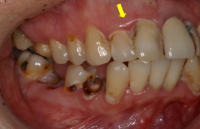

Periodontal [gum] disease will afflict 3 out of 4 adults after age 35, and it’s their major cause of tooth loss. Periodontal disease is the inflammation and infection of the supporting soft and hard tissue surrounding the teeth. In the early stages, it’s called gingivitis which is characterized by redness, ...